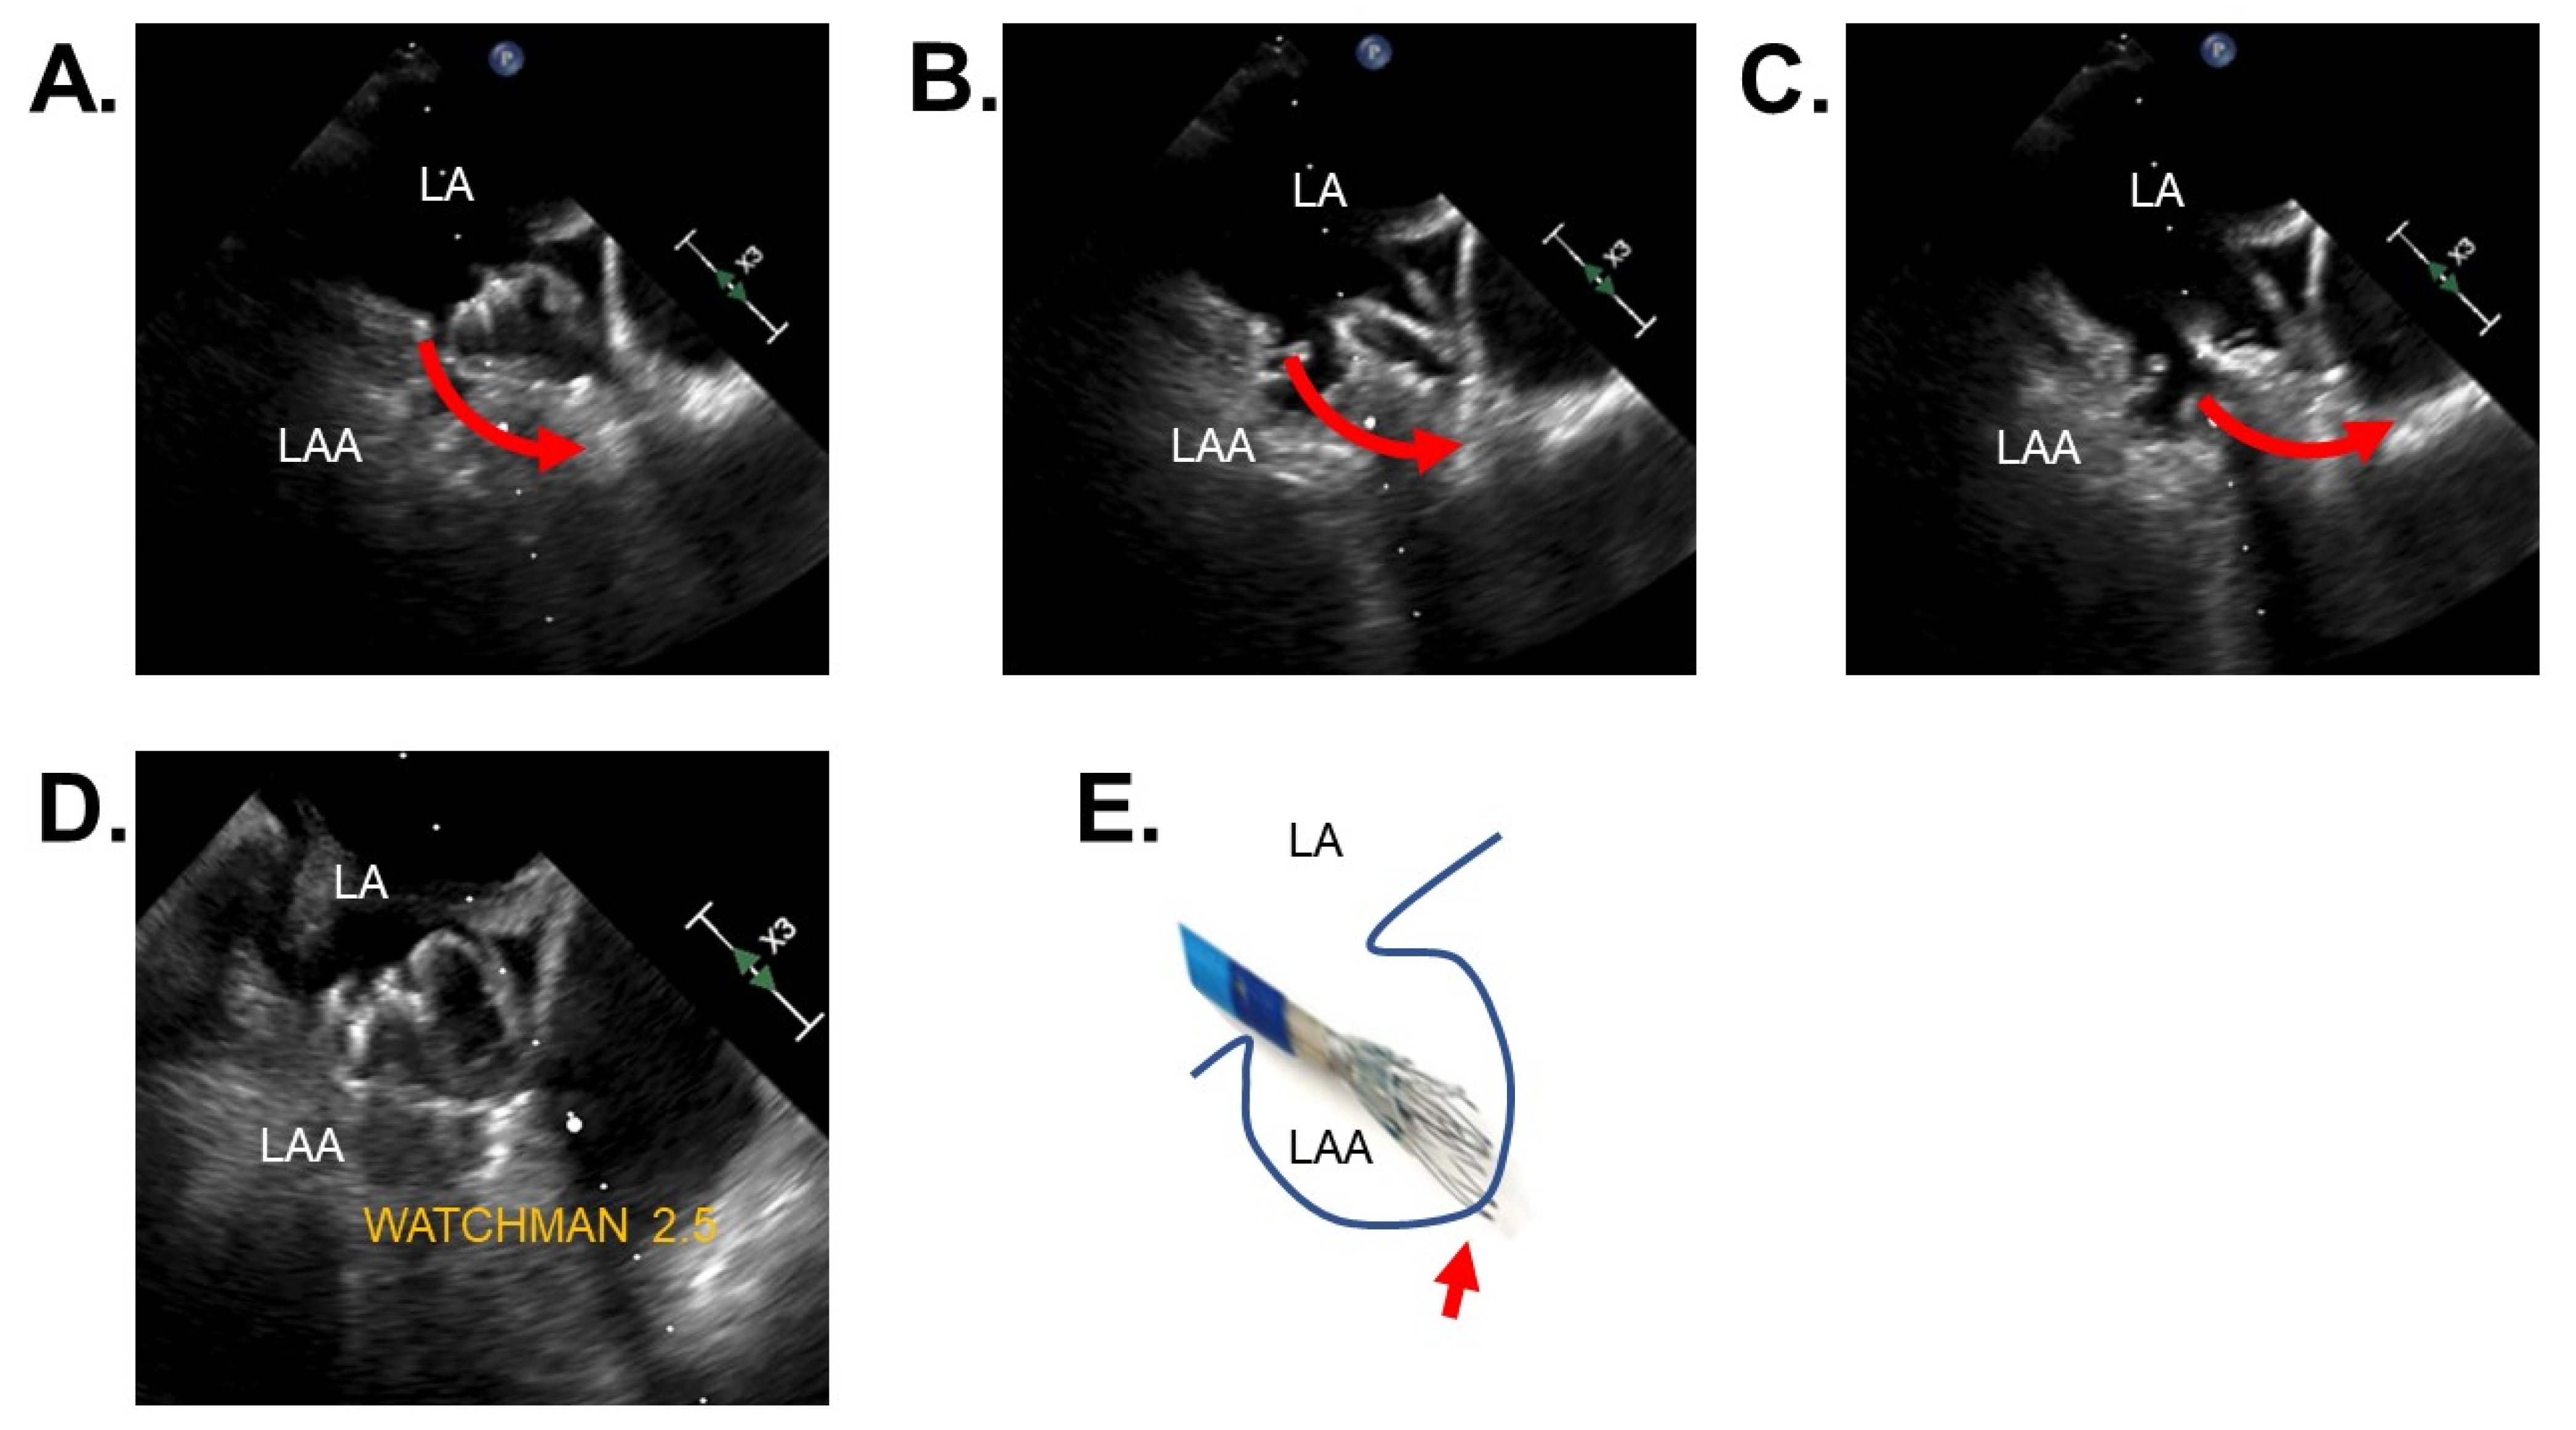

2.2. Procedures